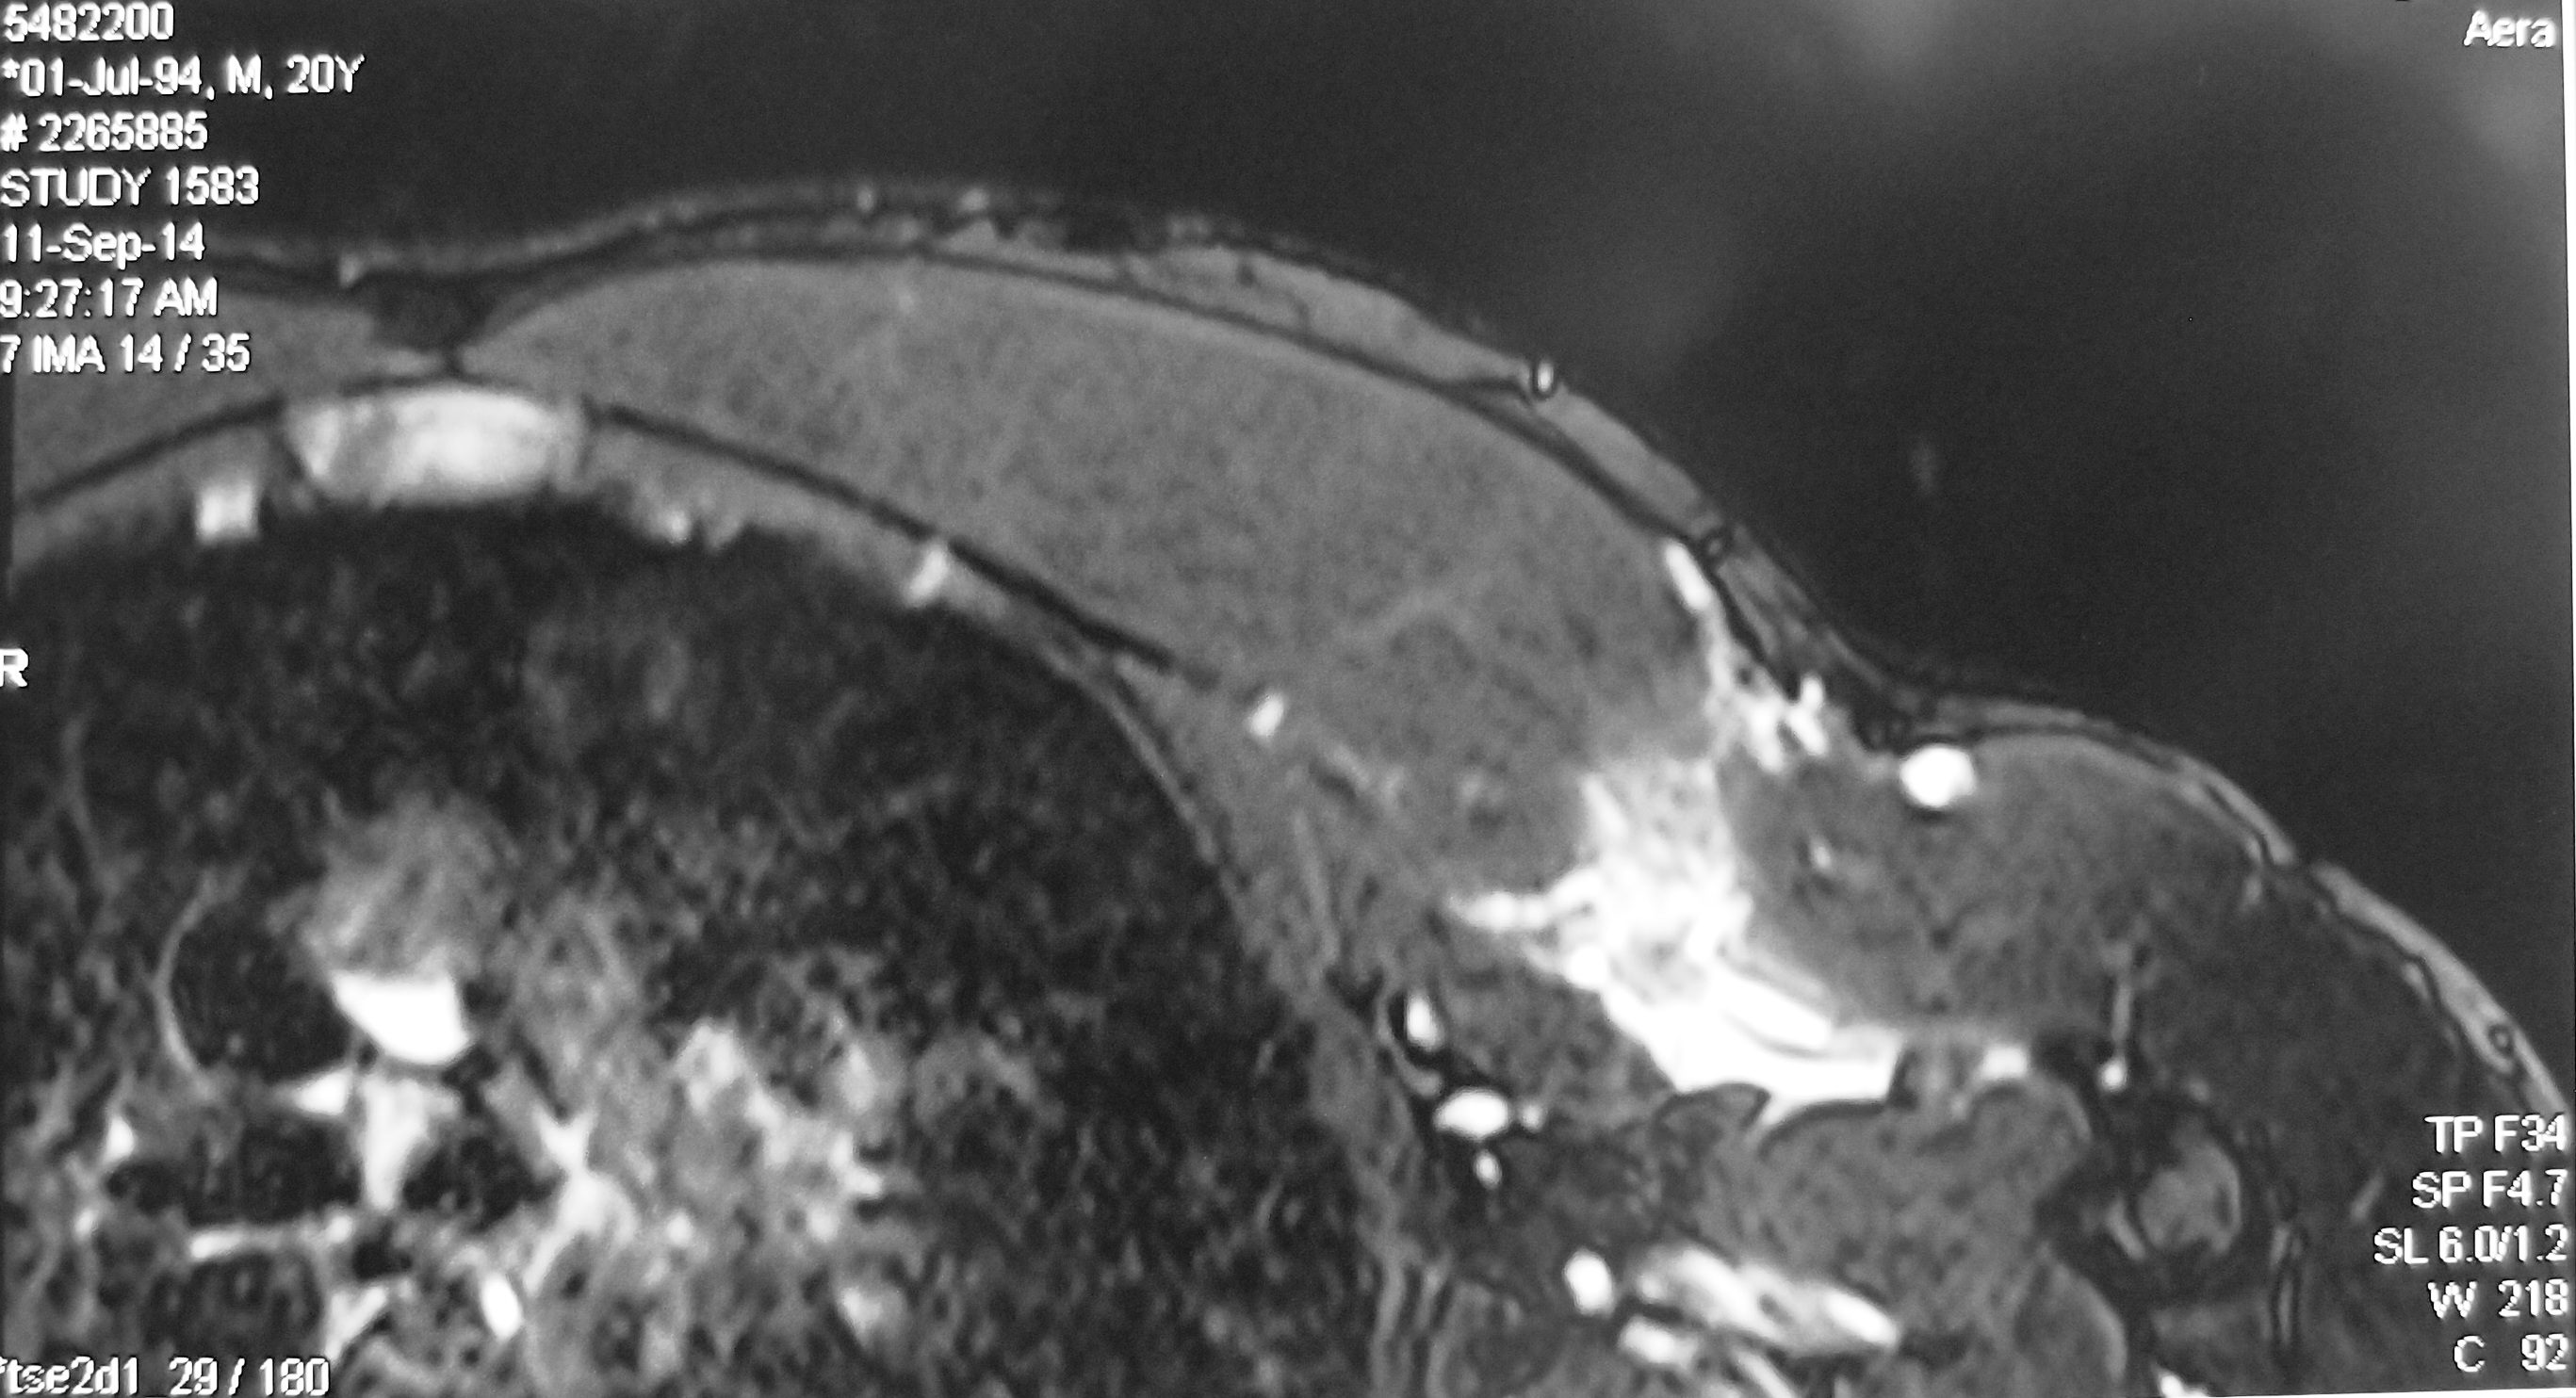

An MRI scan of his left pectoralis major muscle was performed. It confirmed a tear of the left pectoralis major muscle. The muscle and tendon usually rips off the insertion into the humerus bone. In his case, the tendon was still attached to the humerus bone but the muscle was torn in the junction between muscle and tendon (musculotendinous junction).